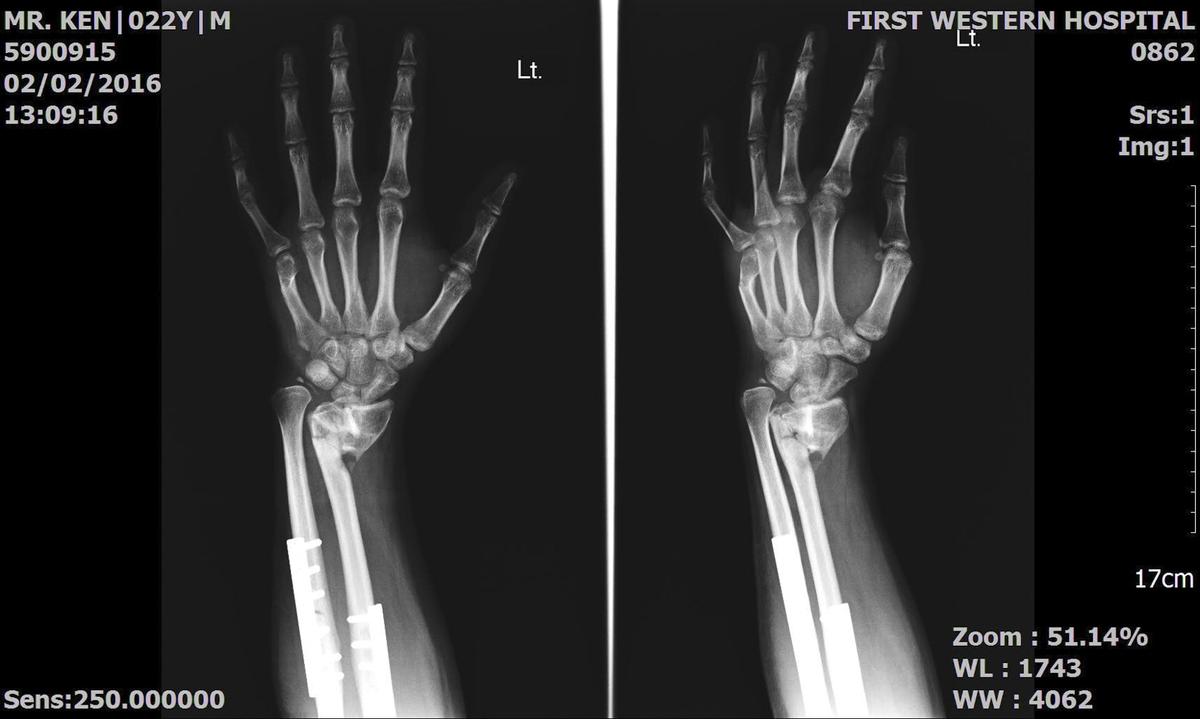

Ken was left with a severe wrist injury.

The doctor said that if Ken does not have the surgery then he will not be able to use his wrist anymore so Eri and Tosh have decided to help him.